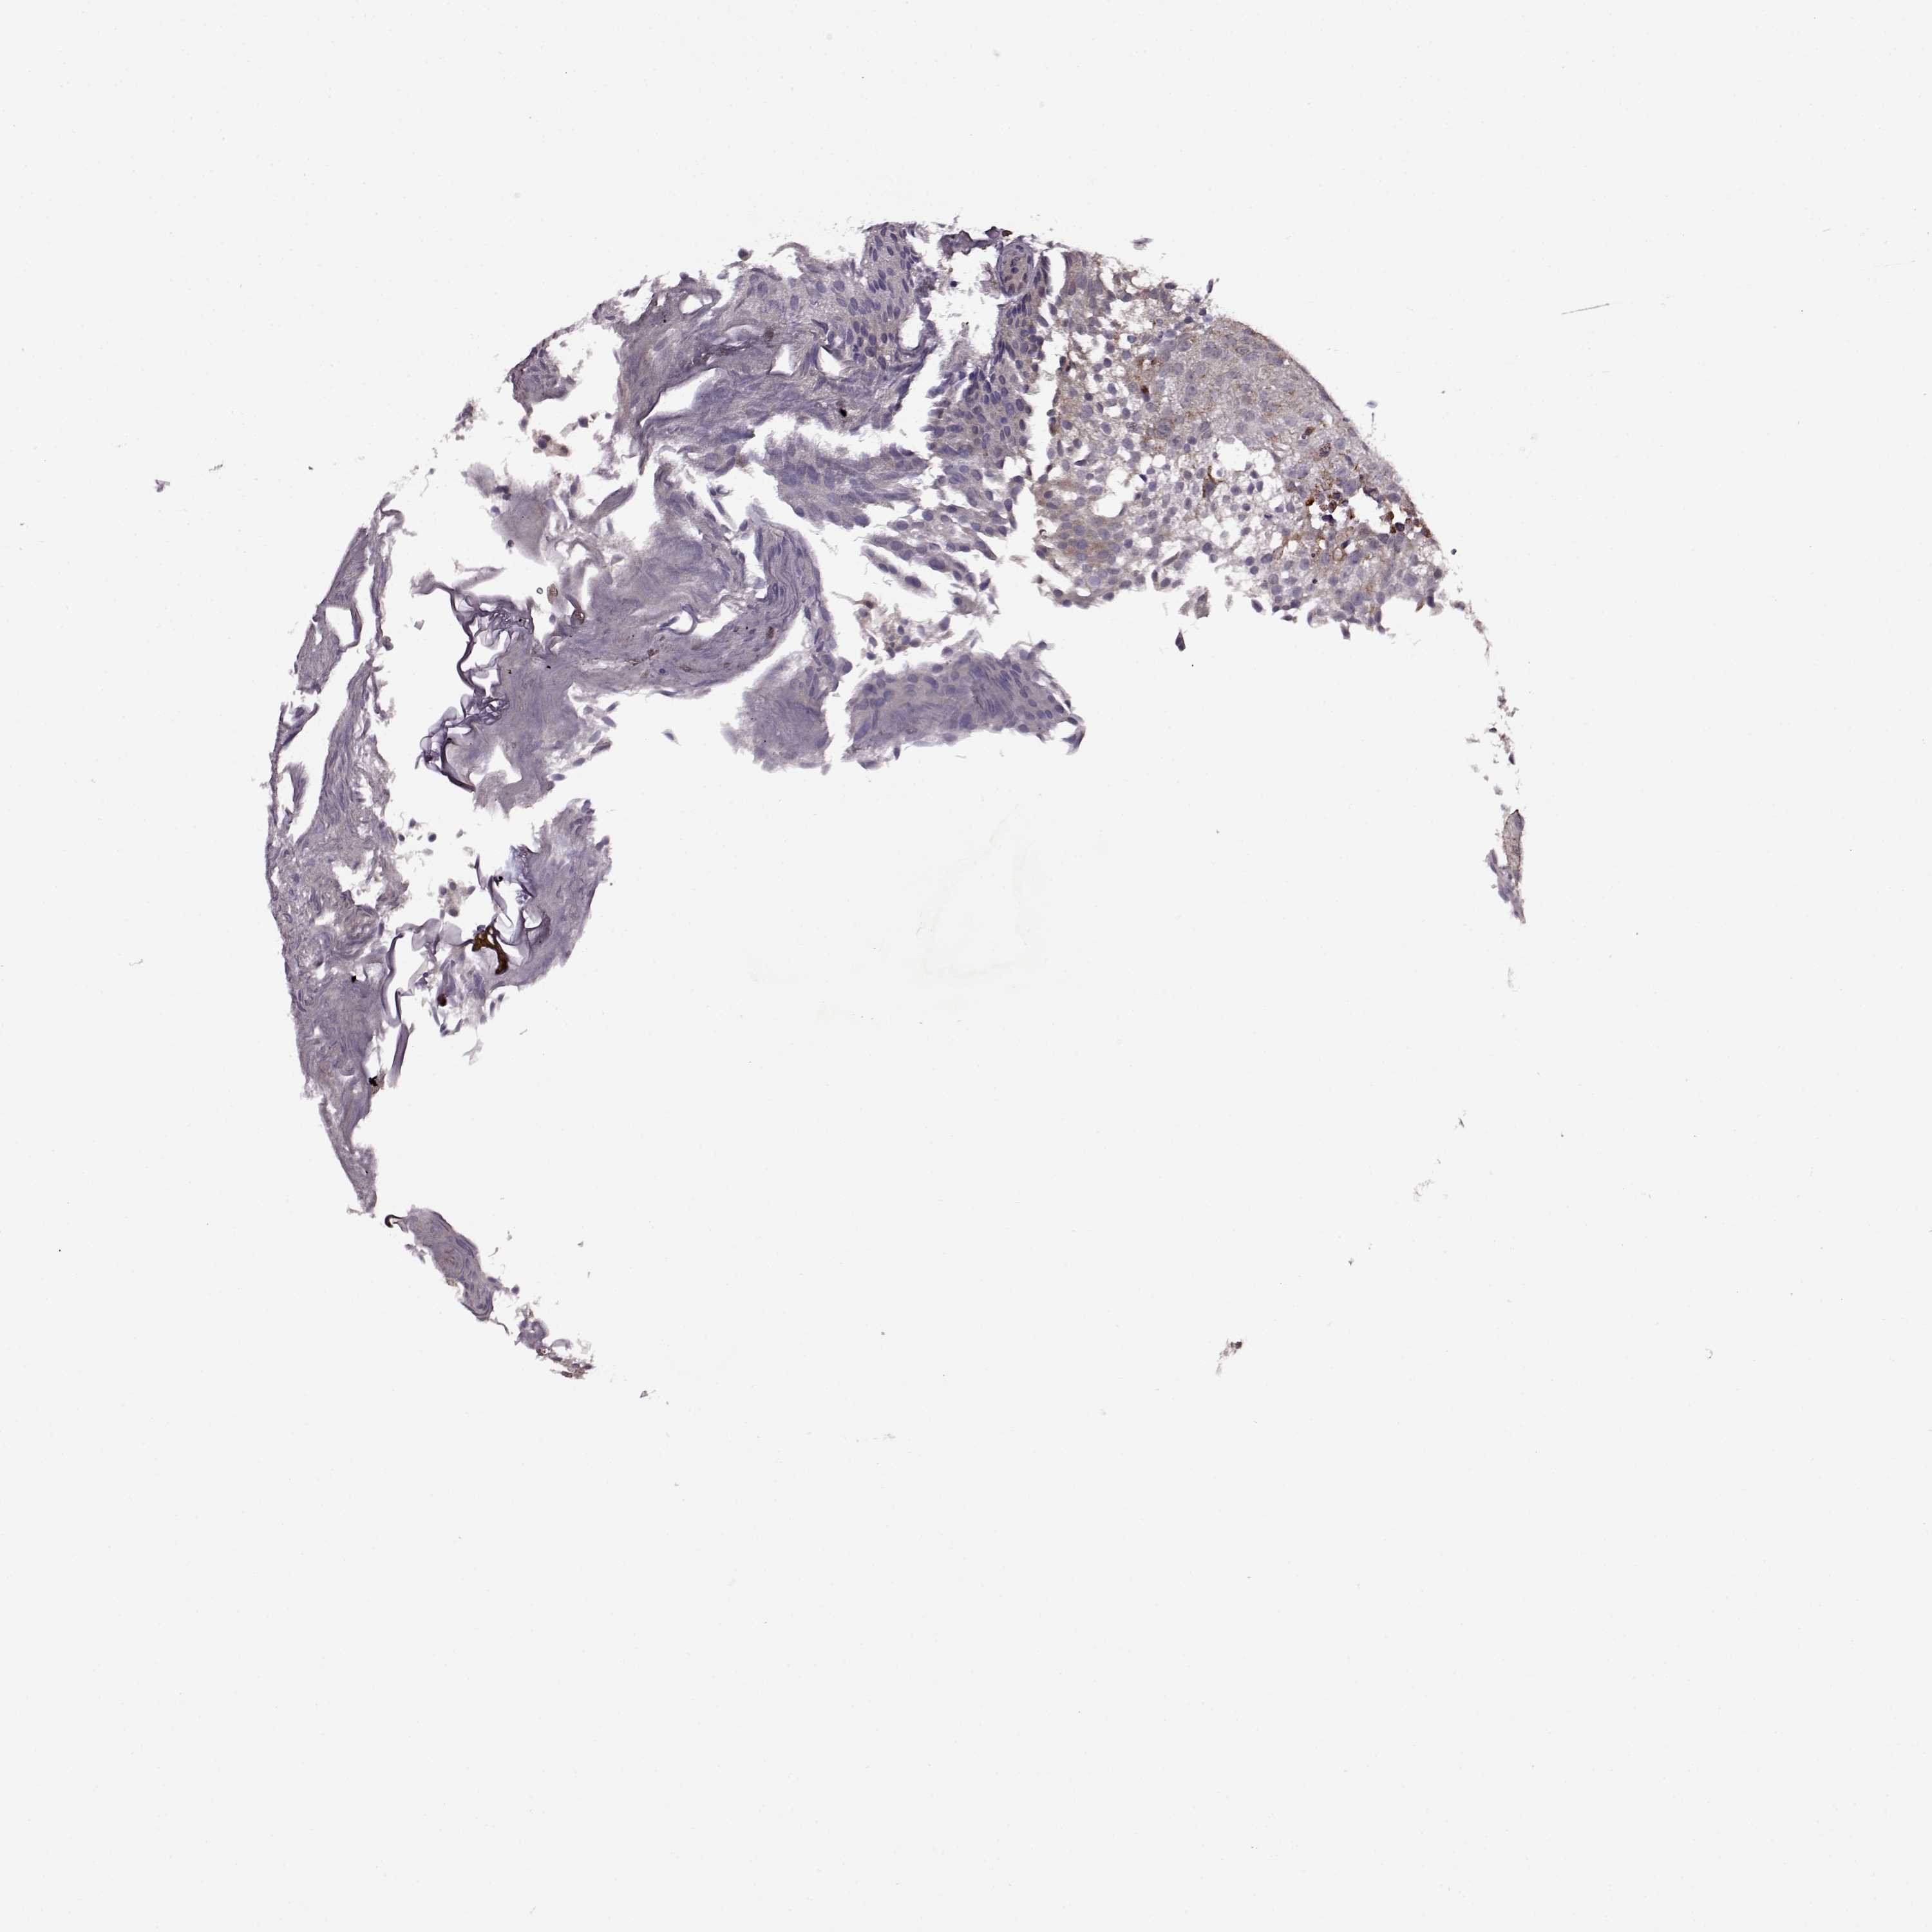

UROTHELIAL CANCER - Protein expressioni

A mouse-over function shows sample information and annotation data. Click on an image to view it in a full screen mode. Samples can be filtered based on level of antibody staining by selecting one or several of the following categories: high, medium, low and not detected. The assay and annotation is described here.

Antibody stainingi

Antibody staining in the annotated cell types in the current human tissue is reported as not detected, low, medium, or high, based on conventional immunohistochemistry profiling in selected tissues. This score is based on the combination of the staining intensity and fraction of stained cells.

Each image is clickable and will lead to virtual microscopy that enables deeper exploration of all samples and also displays staining intensity scores, fraction scores and subcellular localization as well as patient and tissue information for each sample.

Antibody HPA075540

Staining

High

Medium

Low

Not detected

Intensity

Strong

Moderate

Weak

Negative

Quantity

>75%

75%-25%

<25%

None

Location

Nuclear

Cytoplasmic/membranous

Cytoplasmic/membranous,nuclear

Urothelial carcinoma, High grade

Urothelial carcinoma, NOS

Urothelial carcinoma, Low grade